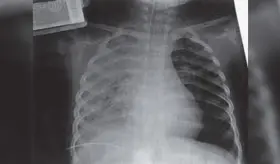

El virus respiratorio sincitial (VRS) es una de las principales causas de hospitalización pediátrica en Puerto Rico, especialmente en lactantes y recién nacidos, debido a su capacidad para causar bronquiolitis y neumonía.